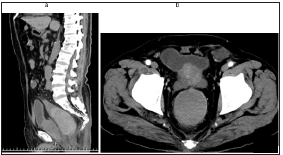

Figure 2:

(a): Sagittal section of abdominal plain computed tomography showed a large highly absorbed mass (white

arrows) which was 9*9*5cm in size in the rectum from rectosigmoid to above the peritoneal reflection.

(b): Axial section of abdominal contrast-enhanced computed tomography showed no definitive findings in it

(white arrow heads).